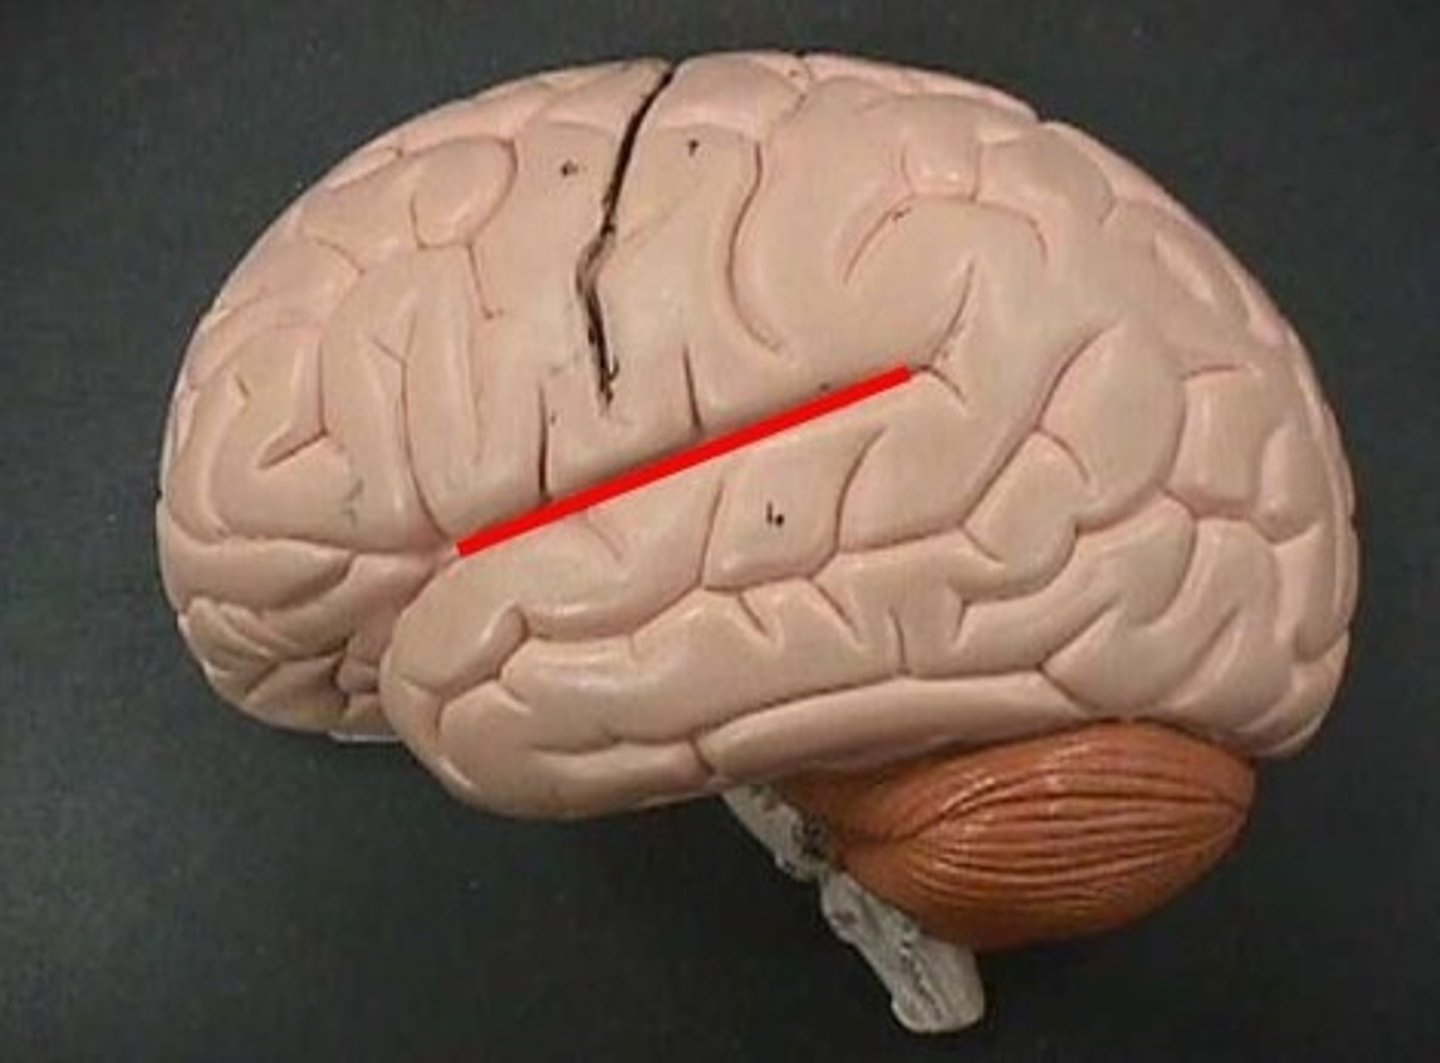

central sulcus

precentral gyrus

postcentral gyrus